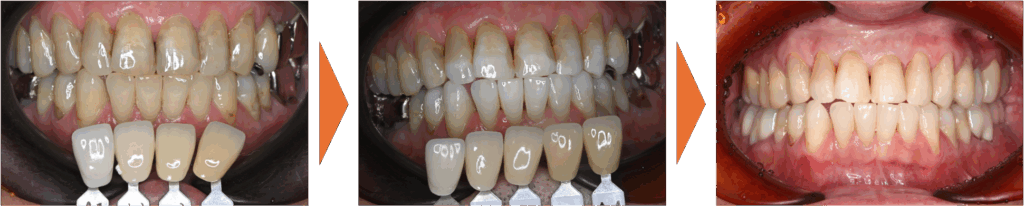

補綴治療は、先にホワイトニングを行い、お口全体のトーンを明るくしてから、その色に合わせて精密なセラミックの被せ物を作製することになりました。

セラミックを作製する前に全体的なトーンアップを行い、基準となる色を作りました。 - 審美修復(セラミック治療):

セラミックは一度作ると後から色が変えられません。そのため、先にホワイトニングを行って理想の白さを手に入れてから、その色に合わせてセラミックを作製することで、周囲の歯と調和した自然な仕上がりを実現しました。 - 「守る」ための設計:

銀歯をすべてセラミックへ置き換え、あわせてホワイトニングを行ったことで、口腔内全体が明るく清潔感のあるお口元になりました。また審美的な向上が得られただけでなく、プラーク(細菌)が付着しにくい環境を整えることができた点も大きな成果です。